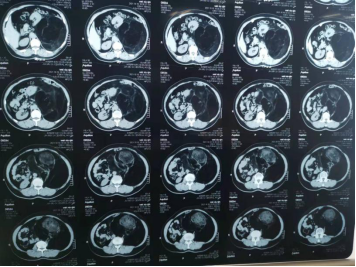

CT报告显示肿瘤直径18厘米

刘女士慕名来到ac米兰官网中文网站二院普外科十病房,经过全面检查发现,在左侧腹膜后有一个直径长18厘米的肿瘤,已经将左肾挤压移位,压迫了腹主动脉。手术是唯一治疗方法。

王夫景介绍,肿瘤占据整个左侧腹腔,上界位于脾脏平面,下界达髂前上棘水平,前方与结肠紧贴,压迫了腹主动脉和左肾,导致左肾被推向剑突下方。由于肿瘤和腹主动脉关系密切,紧挨着大血管,导致手术难度变大,如果损伤腹主动脉,就下不了台,还要保证不能损伤肾脏以及结肠等脏器。